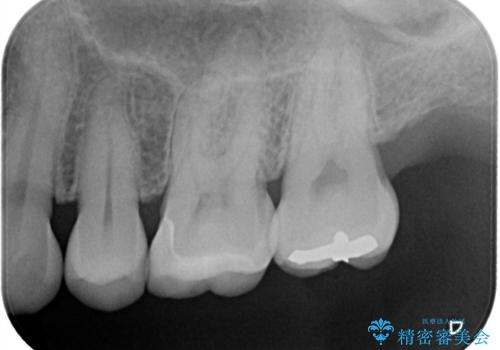

- 主訴:詰め物と歯の境目によごれがいつも溜まっている。フロスを通すと引っかかる。

保険適用のメタルインレーと歯質の境目が、歯質が欠けてしまったのか大きなくぼみ汚れが停滞しやすい状態になっていました。歯冠色材料でのやり替えを希望されたため、セラミックインレーでのやり替えとなりました。

左上6番に入っている保険適応のメタルインレーと歯質との境目(近心側室エリア)に不適部位を認め、そのくぼみに汚れが停滞しやすい状態となっていました。

適合性・審美性を考慮し、セラミックインレーでのやり替えとなりました。